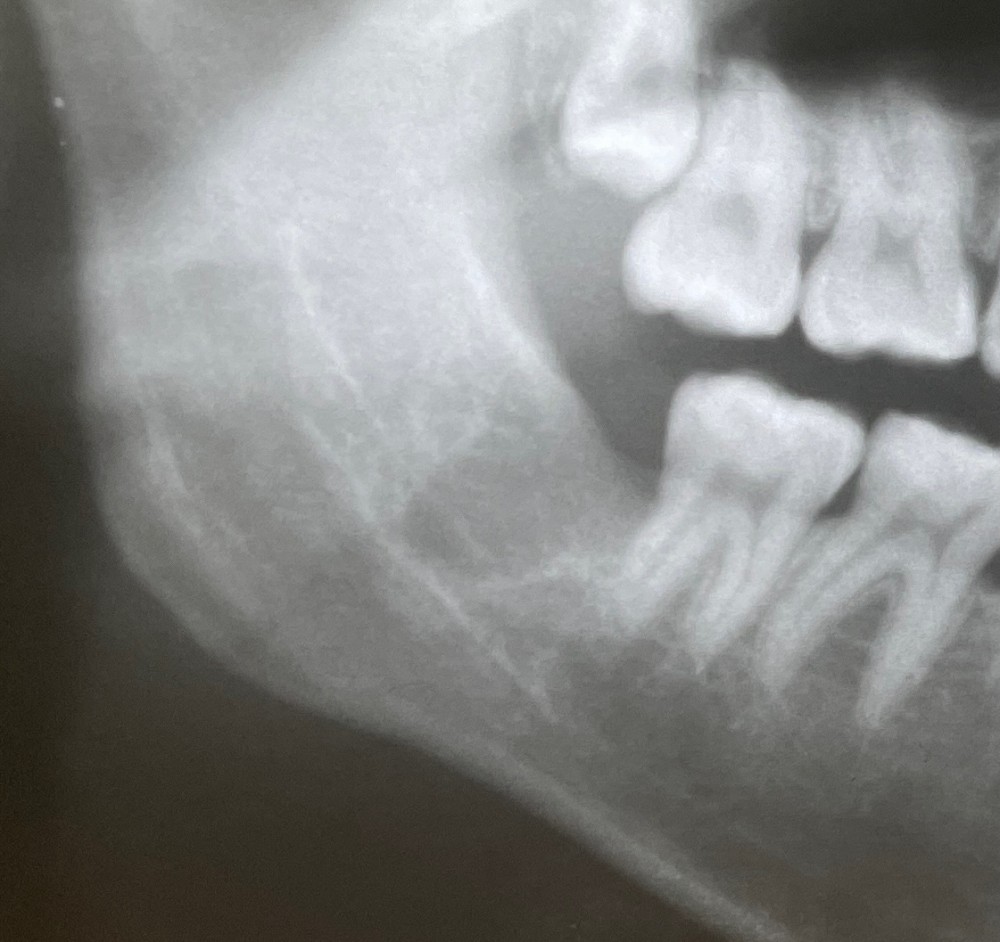

さらにその3年後のエックス線写真がこちらです。

すっかり治療しています。

黒い骨折ラインは確認できなくなりました。

ご本人さまによると、全く違和感なく生活できているそうです。

今回の治療では、手術をすることなく、親知らずの抜歯のみを行い、普通に日常生活を送りながら、治癒したケースです。

人間の持つ治療力は、本当に不思議で素晴らしいと、改めて感じたケースでした。